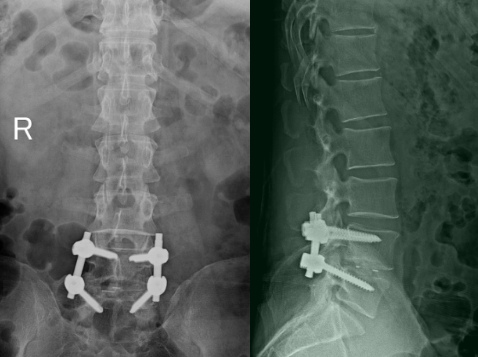

患者董某,51岁;有L4-5椎间盘摘除+椎间植骨融合内固定手术史。本次入院经影像学辅助检查,显示患者腰椎L2-3、L3-4椎间盘膨出,L5-S1椎间盘突出,左侧神经根受压迫。白登彦主任团队结合专科查体确定患者症状责任阶段,并综合评价患者年龄、手术适应症、手术史等多方面因素,为患者制定了L5-S1节段脊柱内镜辅助下突出椎间盘切除联合纤维环缝合手术治疗方案。术后患者恢复良好,对疗效满意。

(白登彦主任为患者行脊柱内镜辅助下突出椎间盘切除联合纤维环缝合手术)